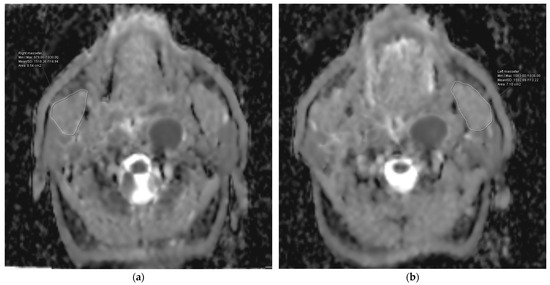

2.5. Post-Processing and Image Analysis